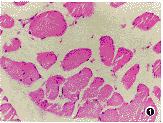

Feulger-DNA染色后甲杓肌及环杓侧肌细胞核呈粉红色(图4),经图像分析甲杓肌和环杓侧肌细胞失神经支配5个月时S期核百分比最高,以后渐减少。

图1 失神经后12个月甲杓肌细胞横切面.肌细胞出现不同程度的萎缩.HE×100 图2 失神经后12个月杓肌纵切面.胶原纤维呈亮细色.VG染色 ×25 图4 失神经后1个月甲杓肌纵切面.肌细胞核呈粉红色,Feulger-DNA染色 ×25